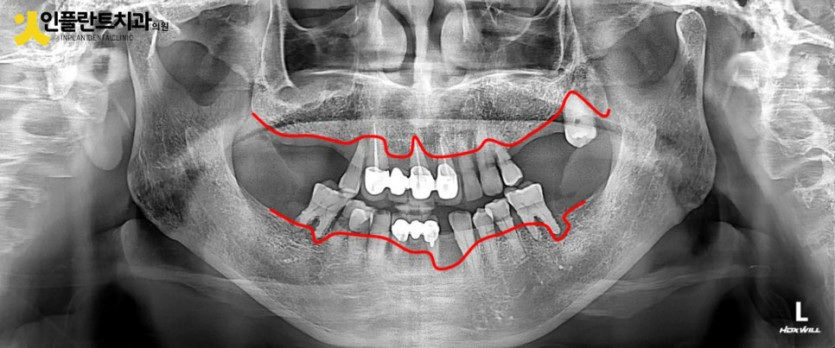

이렇게 발치후 사진을 보시면 이를 뽑은 흔적을 살펴보실 수 있는데요

발치를 하고 나면 그 부위의 뼈가 본연의 역할이 끝나서 흡수되고 부분적으로 차오르는데 최소 3개월 이상의 시간이 소요됩니다.

잇몸뼈는 세월의 흐름에 따라 지속적으로 변하는데 특히 발치 후 이 시기에 많은 변화가 있기 때문에

최종틀니는 필요시 충분한 시간을 지난 후에 제작하시는게 좋습니다.